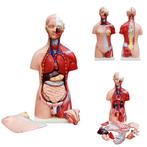

Wat je moet weten over Organen